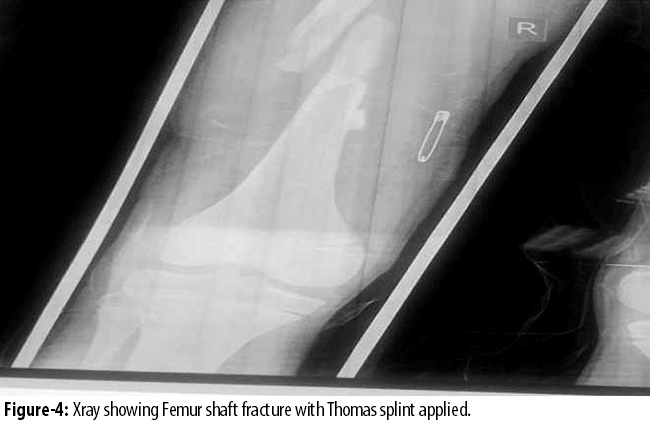

For Patients in group B, Thomas splint traction was applied within 24 hours of admission (Figure 4).

The traction was maintained for about 8-10 weeks depending on the age of the patient. After splint removal, patients were referred for physiotherapy. Follow-up visits were at 2, 4, 12 and 24 weeks after discharge. Patients were available for one year follow-up. Radiological union, limb alignment, limb length discrepancy (LLD) and wound-site infections were assessed at each visit.